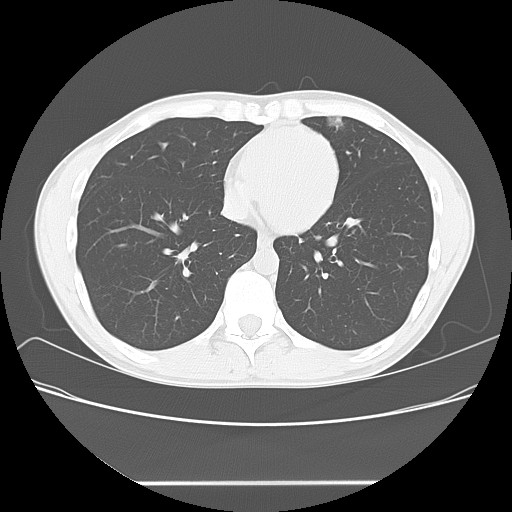

2006年入院治療の退院日から10年。 かなり大きな節目なんだが、なんだろうこの軽い感じは(笑)。 「10年生きたんだぁ」くらい。 変わったような変わっていないような。 当時は10年後なんて全く考えていなかった。 今も10年後は考えていないが・・・。 退院前日の2006/10/31は46.6kgだった。 今日計ったら54.8kg。体脂肪は16.6%。 とても健康にストレスなく生活できていることに、治療当時から現在に至るまで、関わった人全員に感謝の気持ちです。 マーカー、CT画像、問題なし!! 血液検査結果もほとんど文句なしの正常値。 そうだなぁ、数値に出ない異変としては、肩凝りかなぁ。 一旦夏になくなったと思ったが、初秋から再発。 マウスを左手にしたり、シップ貼ったり、最近はホッカイロ貼ったり。 で、一向に良くなる気配がない。 やはり四十肩なのか。 でも肩の可動域は問題ない。動かせないような痛みも無い。 結局色々考えてたどり着いたのは「変形性頚椎症」ではないかと。 肩凝りや頭痛がダラダラと続くようになるという症状がピッタリ当てはまる。 さて、改善策がなかなか難しい。 整形外科行ってもレントゲン撮って湿布をくれるだけだろう。 そんなことに大金を出すならまずは300円/回のプールで泳ごうと思う。 重力から開放して全身運動をするのが一番良いらしい。 2015年の目標は少しでも良いから水泳を再開する、だな。 マーカー、CT画像、問題なし!! 通常の血液検査結果も文句なしの正常値がズラ~っと並んだ!! 間違いなくヨメの食事のおかげである。ほんとうに感謝である!! ちなみに最近少々腰周りの肉付きが気になっていたのだが・・・。 左から2013年12月、2013年06月、2012年12月と背骨の位置は合わせて並べてみた。 6月まではあまり変化がなかったが、この半年で明らかに違う。 背中側の脂肪がやや増えてはいる。 でも最も大きな違いは、腸なのか、やたらと内臓が膨れている・・・。 一言で言うと食べすぎ?!?! 食事は野菜中心ではあるが、確かによく食べているw。 せっかくスーツのウエストを詰めたんだからこれ以上にならないようにしたい。 「腹八分目を心がける」かな。